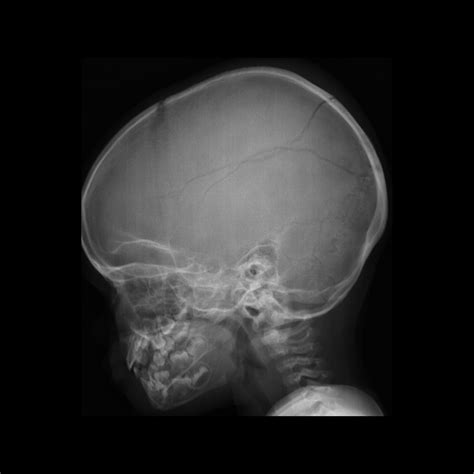

A Baby Skull Xray is a radiographic imaging technique used to visualize the bones of a baby's skull. This non-invasive procedure is essential for diagnosing various conditions, including fractures, deformities, and developmental abnormalities. The X-ray images provide a detailed view of the skull's structure, helping healthcare providers make informed decisions about treatment and care.

Interpreting Baby Skull Xray results requires a trained eye and a deep understanding of pediatric anatomy. Here are some key points to consider:

• Bone Density: The density of the bones can indicate the presence of fractures or other abnormalities.

• Skull Shape: The shape of the skull can provide insights into developmental issues or deformities.

• Fontanelles: The soft spots on a baby’s skull, known as fontanelles, should be checked for proper closure and any signs of swelling or bulging.

• Sutures: The sutures, or the fibrous joints between the skull bones, should be examined for any signs of premature fusion or separation.

Several common findings can be identified through a Baby Skull Xray. Understanding these findings is essential for accurate diagnosis and treatment:

• Fractures: Visible cracks or breaks in the skull bones.

• Deformities: Abnormal shapes or structures of the skull.

• Infections: Signs of infection, such as bone erosion or swelling.

• Tumors: Abnormal growths or masses within the skull.

• Developmental Abnormalities: Issues with the development of the skull, such as premature fusion of sutures.